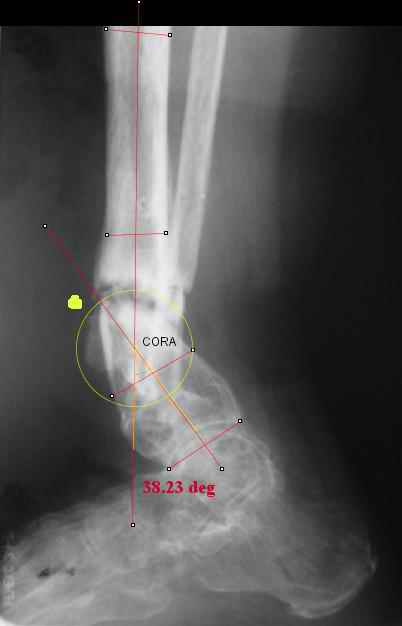

I played with your image using some orthopedic software we have been developing for digital

image analysis.

What you see marked up is the intercept of two mid-line tool centre lines, used to define the CORA. An angle tool gives the angular deformity and a circle tool is applied to show that a correction around the CORA through the old # will restore alignment without much translation.

Maybe my "embedded software" is obsolete but it hints me to place hinges at the yellow point - this must result with alignment and some lengthening without translation. What do you think?

I looked at your image. I presume your yellow marker is the hinge axis? I think this should be at the CORA.